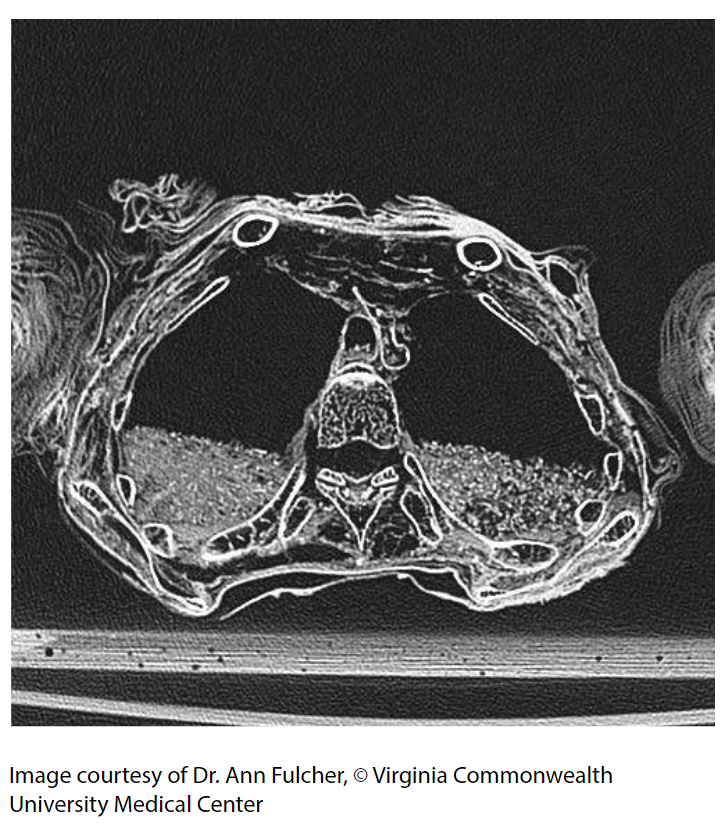

This CT image shows an axial (cross-sectional) image of Ti Ameny Net’s torso, around her chest area showing her lungs and vertebrae. The image reveals the packing material inside the body cavity and the many layers of linen wrapped around the arms.